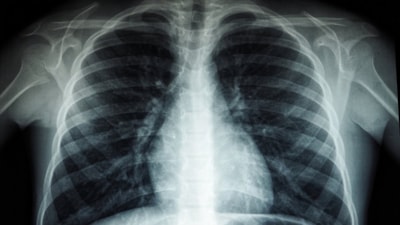

Sağlık Bakanı Fahrettin Koca, üst solunum yolu enfeksiyonlarının arttığı bir dönemde olunduğunu belirterek uyarıda bulundu. Bakan Koca, "Bağışıklık sistemi baskılanmış hastalarda, yaş gibi sebeplerle risk grubunda olan kişilerde enfeksiyonlar ciddiye alınmalıdır" ifadesini kullandı.